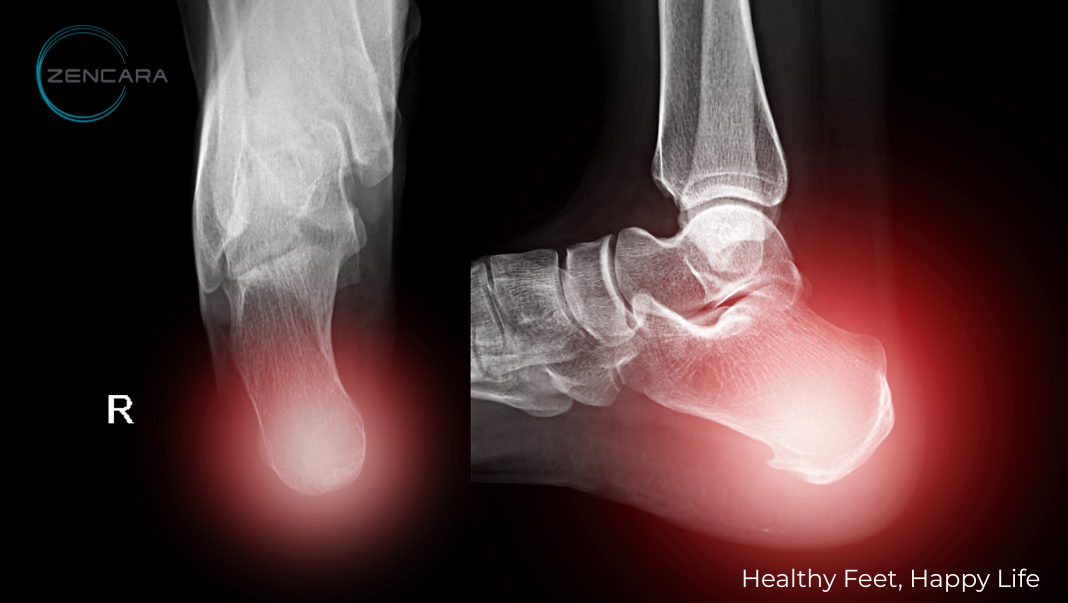

2.2. Gai xương gót

- Gai xương gót là sự lắng đọng canxi tạo thành mấu xương nhọn, thường xuất hiện ở mặt dưới xương gót.

- Cơ chế: Mặc dù gai xương tự thân có thể không gây đau, nhưng nó tạo ra sự kích ứng và viêm tại nơi cân gan chân gắn vào xương gót. Điều này làm gia tăng cảm giác đau và thốn, khiến mỗi bước chân trở nên khó khăn.